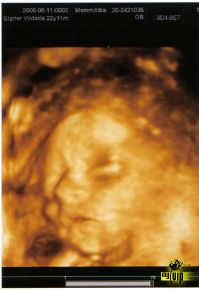

hogy szólithatunk?? Édes a pocaklakótok!!!